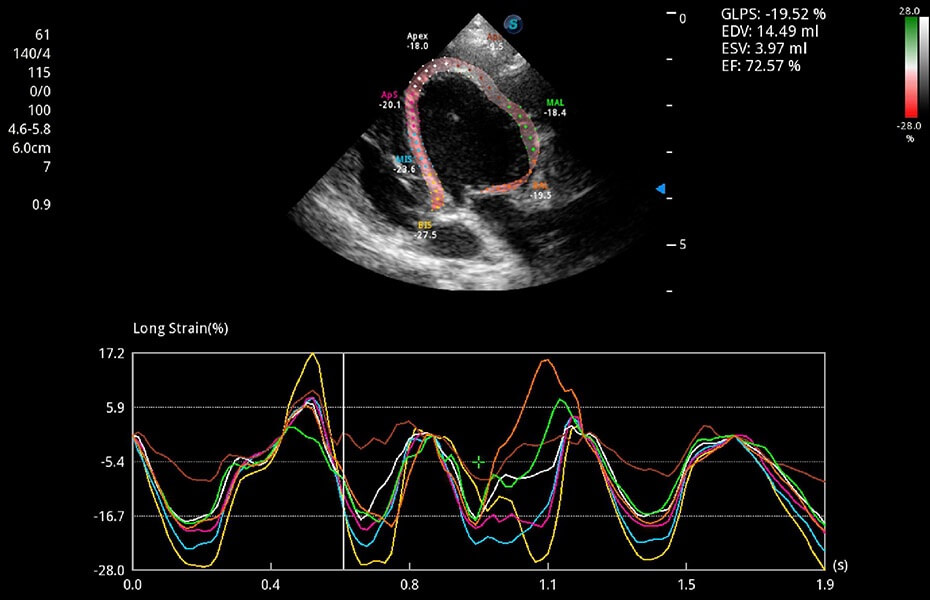

ProPet 60 作为一款高端台式动物超声设备,为动物医生的日常诊断提供了一系列贴合动物临床需求、解决临床实际问题的高级成像功能。凭借全系列高清探头,满足医生对腹部、心脏、生殖、浅表、肌骨等成像的所有需求,切实帮助您提升检查效率,提高诊断信心。

兽用彩色多普勒超声诊断系统